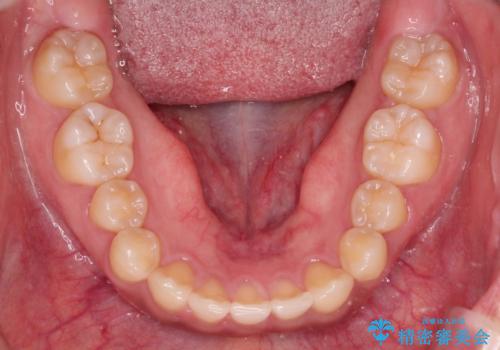

- 前歯の隙間を閉じたいと矯正カウンセリングに来られた患者様です。

マウスピース矯正(インビザライン)を行い短期間で治療が完了しました。